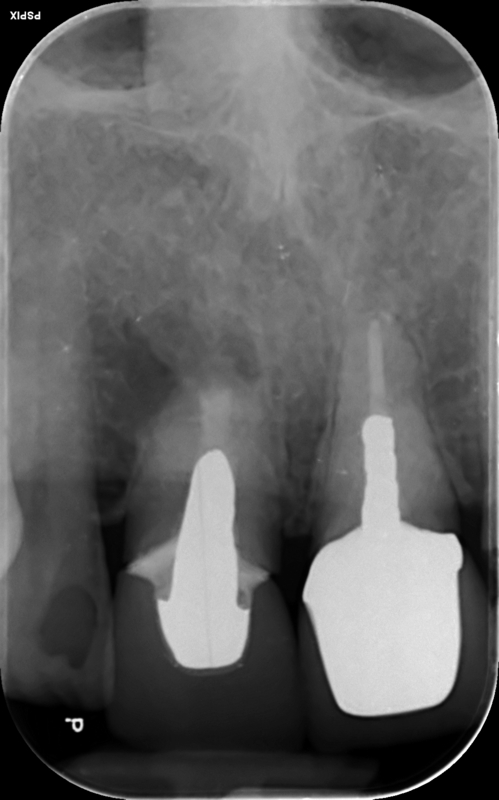

Case 26 – Endodontics

Repeat apicectomy with grafting